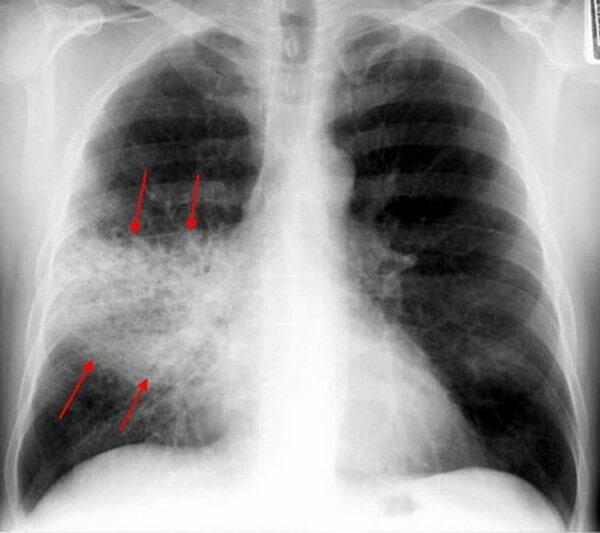

Воспаление легких может быть долевым или очаговым. В последнем случае пневмония характеризуется инфильтративными нарушениями в небольшой зоне легочной ткани с правой стороны, что хорошо видно на рентгене.

При этом возникает кашель и затруднение дыхания, но в некоторых случаях начало заболевания может протекать бессимптомно. Очаговая правосторонняя пневмония у ребенка вызывается вирусами и бактериями, в подавляющем большинстве случаев имеет острое течение.

Могут поражаться целые сегменты или даже несколько сегментов легкого вплоть до всей правой доли. Такое явление наблюдается при очагово-сливном воспалении легких, рентгенограмме показывает на фоне общего затемнения более плотные участки отдельных очагов или полых зон разрушенной ткани.

Рентгенологическое исследование

Крупозная пневмония

При подозрении воспаления легких и для контроля после окончания приема антибактериальной терапии всегда назначается рентгенологическое исследование грудной клетки причем в особых случаях, например, при наличии очага в нижней доле рентген делается в нескольких проекциях (прямой и боковой). В пораженной зоне на снимке различимы гомогенные тени. При микоплазменной инфекции затемнения будут носить неоднородный характер имея тяжистую структуру.

В особо тяжелых случаях, при которых нужна более четкая картина может быть назначена компьютерная томография. Это позволяет определить степень инфильтрации паренхимы легких. Кроме этих методик в индивидуальном порядке могут быть назначены бронхоскопия и флебография легочных сосудов. Данные методы сложны, болезненны и цена их проведения довольно высока.